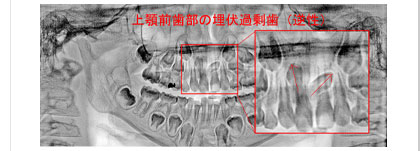

歯の生えてきた位置がおかしい場合。歯の数が多過ぎる場合、少ない場合。

歯並びの凸凹。歯並びの全体の形の不具合。上下の歯のかみ合わせの問題。

実際の歯列不正はさまざまな要因が重なって発生しています。